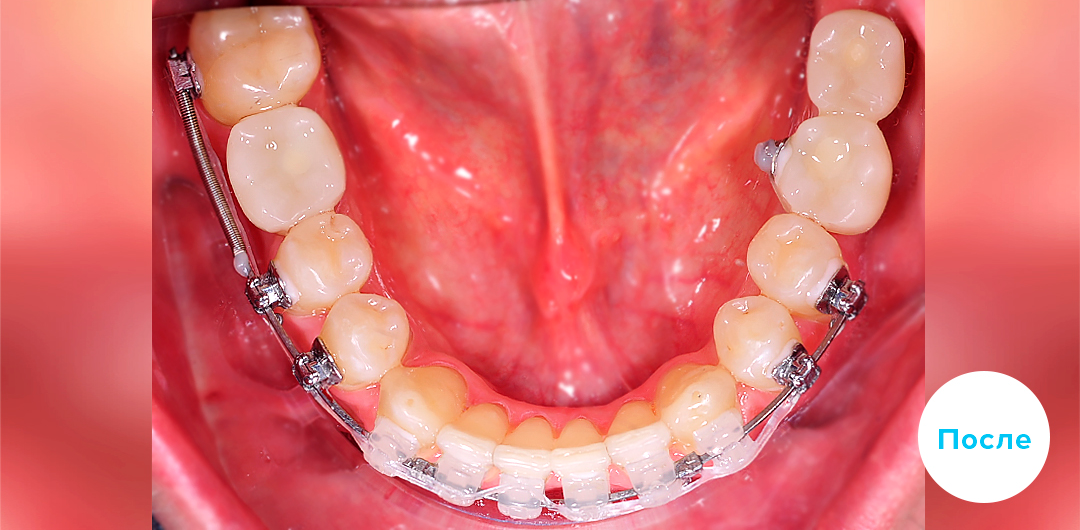

Результаты лечения